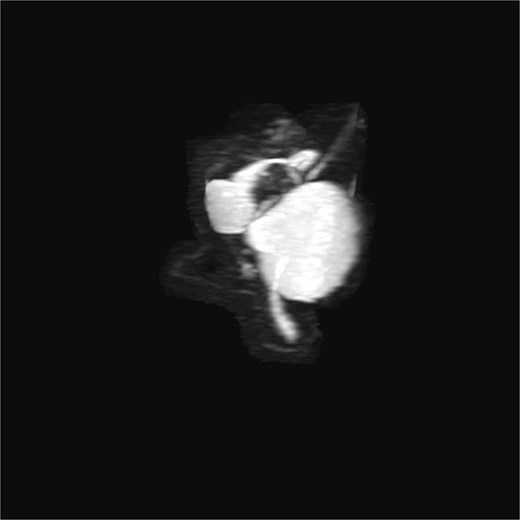

Lab tests showed leukocytosis (15.2 × 103/μl), thrombocytopenia (95.8 × 103/μl), elevated CRP (25.22 mg/dl), procalcitonin (4.49 ng/ml), and total bilirubin (3.5 mg/dl). Liver function was otherwise normal. Ultrasound revealed lithiasic cholecystitis with hydrocholecystosis. Computed tomography (CT) failed to detect duplication (Fig. 1a and b). MRCP confirmed H-type duplicated gallbladder with two independent cystic ducts and mild extrinsic compression of the extrahepatic bile duct (Mirizzi-like pattern) (Figs 2 and 3). MRI sequences (T1 LAVA-Flex and T2 PROPELLER with fat suppression) also demonstrated the duplicated gallbladder and supported the MRCP findings (Fig. 4). No choledocholithiasis was seen.

MRCP (thick-slab 2D coronal oblique) showing duplicated gallbladder (H-type) with two independent cystic ducts and no evidence of choledocholithiasis.

3D T2-weighted MRCP with maximum intensity projection (MIP), showing duplicated gallbladder (H-type) and biliary anatomy.

Most cases are diagnosed incidentally, but preoperative identification via MRCP is crucial in complex or recurrent biliary disease [8] (Figs 2–5). Anatomical variants increase the risk of bile duct injury, bleeding, or incomplete surgery [9]. Surgically, duplicated gallbladders pose technical challenges, especially when inflamed or fibrotic. Higher conversion and complication rates have been reported [7, 11].